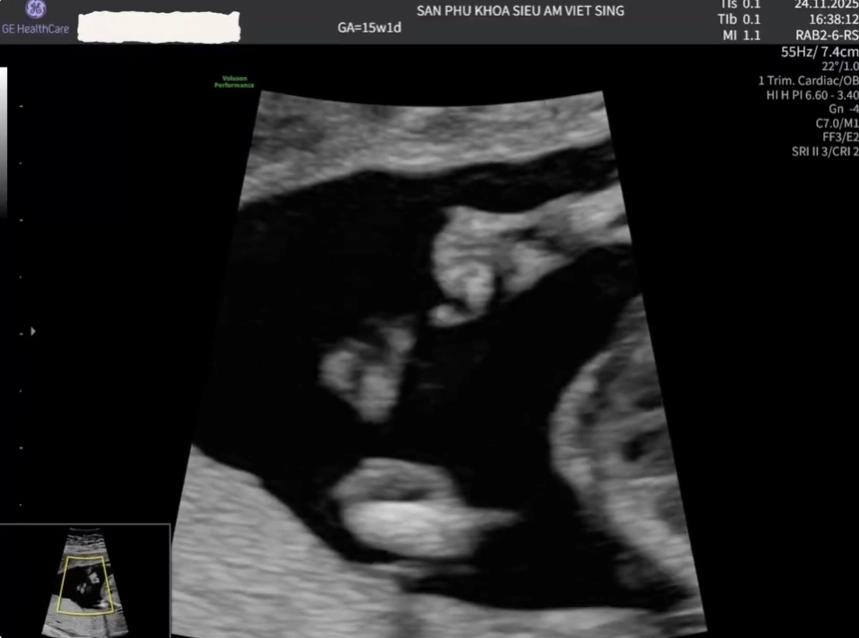

Nang túi lệ thai nhi (Dacryocystocele)